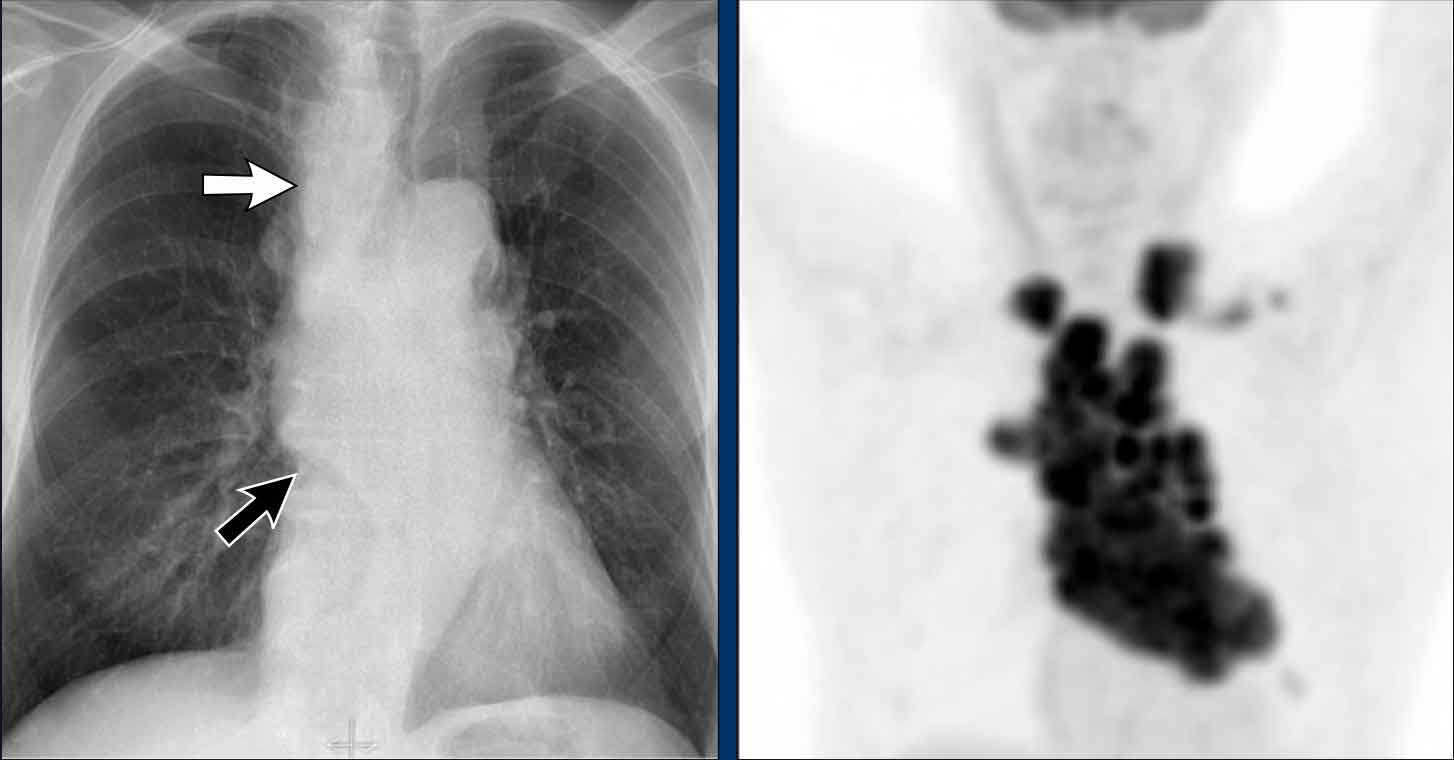

Hidden area (5): Mass Behind the First Rib

In some patients, an accessory joint at the anterior aspect of the first rib may simulate a mass, as we learned earlier.

However this area is also a "hidden zone", where true lesions can be masked.

• In this case, a small lung carcinoma was obscured by the left first rib on the PA view.

• On the lateral film, the lesion is visible in the retrosternal space.

Continue with the PET-CT...

Subsequent PET-CT imaging confirmed a hypermetabolic tumor (arrow), with metastases to the bone and liver.

• Diagnosis was confirmed via biopsy of an osteolytic metastasis in the iliac bone.